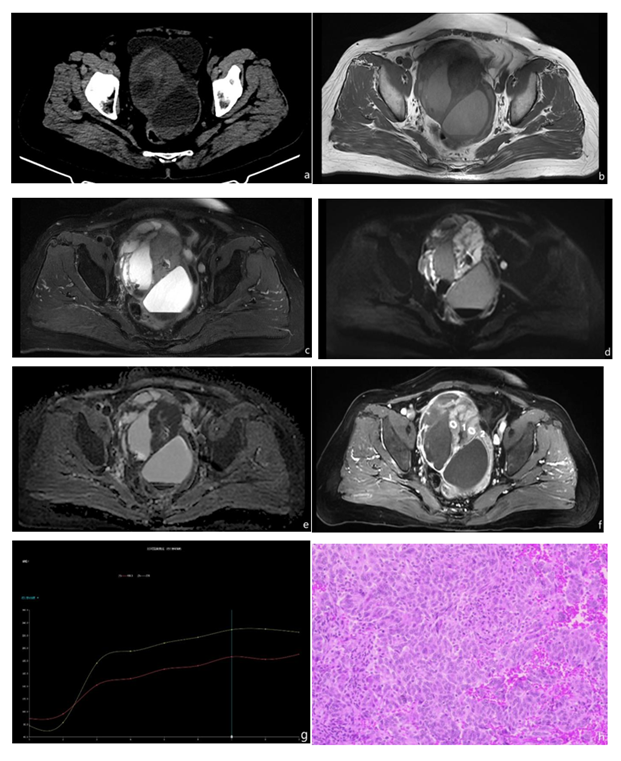

A 71-year-old woman presented with more than two years of upper abdominal pain. Her medical history included hysterectomy for uterine fibroids. On pelvic examination, the uterus was absent, there were no masses at the vaginal cuff, and a firm, poorly mobile, non-tender mass was palpated in the pelvic cavity. Laboratory tests showed an elevated CA125, while liver and renal function, as well as Alpha-fetoprotein (AFP), Carcinoembryonic antigen (CEA), CA19-9, CA15-3, and HE4 levels, were within normal ranges. CT revealed a large cystic–solid mass in the right adnexal region with a fluid-fluid level suggestive of intratumoral hemorrhage (Figure 1a). MRI confirmed a large complex cystic–solid lesion in the same region. On T1-weighted imaging (T1WI), the mass displayed heterogeneous signal intensity with mixed iso- and hyperintense areas (Figure 1b). T2-weighted imaging (T2WI) and fat-suppressed T2WI showed markedly heterogeneous signals across high, intermediate, and low intensities, with a fluid-fluid level consistent with hemorrhage (Figure 1c). Diffusion-weighted imaging (DWI) with b-values of 50 and 800 s/mm² demonstrated progressive hyperintensity in the solid components (Figure 1d), with corresponding hypointensity on the apparent diffusion coefficient (ADC) map, indicating restricted diffusion; the cystic portions did not restrict diffusion. Persistent hypointense areas and the fluid-fluid level within the lesion supported a hemorrhagic cystic–solid tumor (Figure 1e). Dynamic contrast-enhanced (DCE) MRI showed abundant tumor vascularity with rapid early enhancement and persistent enhancement (Figure 1f), and the time–intensity curve was type II (Figure 1 g). The patient underwent laparotomy for the right adnexal region. The uterus and left adnexal region were absent, and a large right adnexal cystic–solid mass, measuring approximately 10.5 cm in diameter, was identified. Histopathology demonstrated ovarian adult granulosa cell tumor with sarcomatoid transformation (Figure 1h).

Figure 1: Ovarian adult granulosa cell tumor with sarcomatoid transformation. a CT showed a large cystic-solid mass in the right adnexal region, containing a fluid-fluid level suggestive of intratumoral hemorrhage. b On T1WI sequences, the mass demonstrated heterogeneous signal intensity with mixed isointense and hyperintense areas. c T2WI and fat-suppresse T2WI sequences showed markedly heterogeneous signals comprising high, intermediate, and low intensities, along with a fluid-fluid level, further supporting the presence of hemorrhage. d DWI with b-values of 50 and 800 showed that the solid components of the tumor exhibited progressive hyperintensity. e The ADC showed that the solid component of the tumor was a low signal, In contrast, the cystic portions showed no diffusion restriction. Persistent hypointense areas and a fluid-fluid level within the lesion were consistent with a hemorrhagic cystic-solid tumor. f DCE scanning showed the blood supply of the tumor region was abundant, and it was obviously enhanced in the early stage and continuously. g The dynamic enhanced scan curve showed a type II time-intensity curve. h The pathology results showed that the tumor cells were of varying sizes, with oval, spindle-shaped or irregular nuclei, characteristic Call-Exner bodies, and abundant cytoplasm that was acidic and presented a watery-like or irregular arrangement